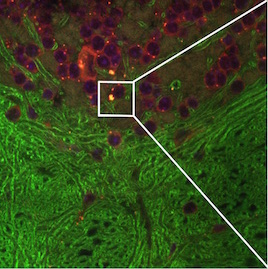

Correlative microscopy is an integration of different microscopy technologies including conventional light, confocal and electron transmission microscopy [6]. Correlative microscopic images usually involve linear or non-linear distortions which are caused by the differences between imaging systems and processing steps. Therefore, the first step of most correlative microscopy based applications is to do registration between two or more microscopic images. An example of correlative microscopic images is presented in Fig. 1.

Refer to caption

(a) Confocal Microscopic Image

(b) Resampling of Boxed Region in Confocal Image

(c) TEM Image

Figure 1: Example of Correlative Microscopy. The goal is to align (b) to (c).